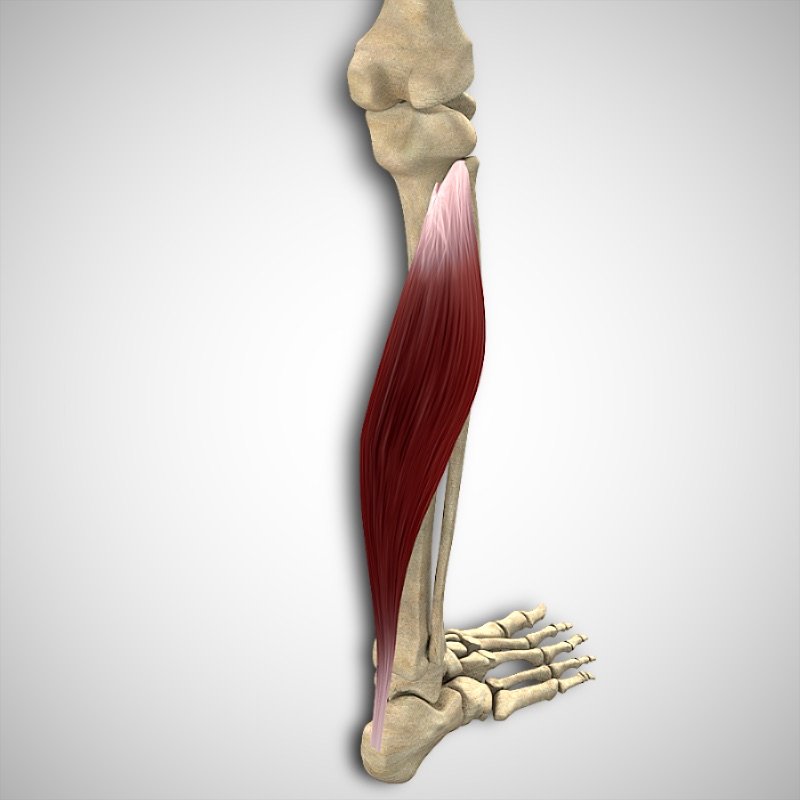

ORIGEN

- Línea del sóleo en la Tibia

- Cabeza del peroné

INSERCIÓN

- Calcáneo a través del tendón de Aquiles

ACCIÓN

- Flexión plantar de la articulación tibioastragalina